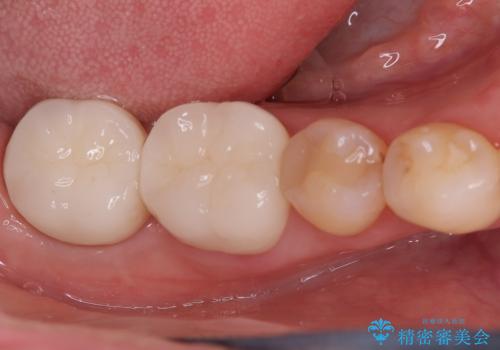

繰り返すプラスチックの欠けを解消。広範囲の修復に適したセラミッククラウン

担当医 河口智英